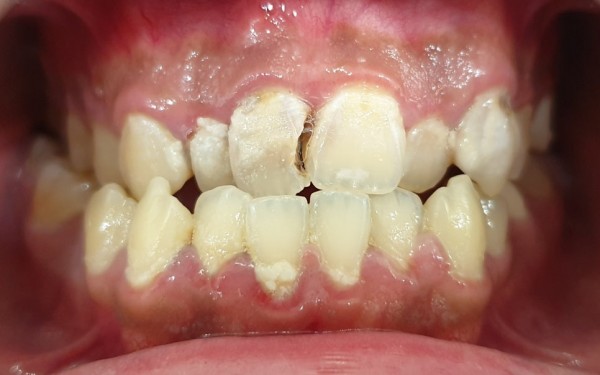

구강 검진 결과, 예상보다 상황이 심각했습니다.

오랜 기간 방치로 인해 전체적으로 충치가 상당히 진행된 상태였습니다.

특히 치열이 불규칙하게 배열되어 있어 칫솔질이 어려운 부위에

집중적으로 우식이 발생한 것으로 보였습니다.

상악 좌측 제1대구치(#16)에는 기존에 인레이 치료를 받으셨던

부위 아래쪽으로 2차 우식이 진행되어 인레이가 탈락된 상황이었고,

앞니 부분에도 상당한 우식이 관찰되었습니다.

전반적으로 여러 치아에 걸쳐 치료가 필요한 상태였죠.